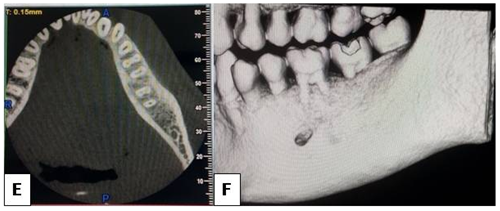

Figure 3 E- showing axial section of a CBCT image showing no cortical expansion. F- 3D section of the same showing horizontal bone loss and no cortcal expansion.

Even in the cases where the lesion is associated with roots of teeth, there is no increased mobility of the teeth or changes in their color. The present case too had normal appearing teeth associated with the lesion. Pulp vitality is not likely to be altered. However, due to traumatic force, cystic expansion may increase the root pressure resulting in a temporary reduction in the pulpal response to the electric test which holds good in our case too.9-15 Clinically, there are no soft tissue changes, pain or paresthesia. In the early phases, there is usually no bone expansion while in the later phase; there can be bone expansion. In our case there was no bone expansion.12 Periapical radiographs are ideal for early radiographic assessment but these radiographs fail to show the whole extent of the lesion. Panoramic radiography, computed tomography and magnetic resonance are more precise imaging modalities in the diagnosis of these cysts. In our case the cyst was an incidental finding in an IOPA the extent of which was found later by an OPG.8 Radiographically, these lesions appear as a well defined radiolucent defect with diameter in the range of range 1 to 10 cm as seen in our case.10 The cysts usually presents as scalloping pattern between the roots of the involved teeth which was seen in our case too where the cyst scalloped between the roots of 36 and 37.11 The structure of the mandible canal may in some cases be preserved and in other cases not. There is no resorption of the teeth roots. The lamina dura may or may not be involved.4 In our case, the lesion involved the mandibular canal, with loss of lamina dura but no root resorption. Histopathological examination reveals a thin band of vascular fibrous connective tissue lacking an epithelial lining. In our case also histopathological examination revealed bone tissue and extravasated RBCs without lining epithelium.13 Treatment is surgical operation which consists of evacuation of the content, cochleation of the cavity in order to stimulate bleeding in the cavity. The wound is then sutured. This is followed by the formation/creation and organisation of a clot, and healing by the formation of new bone.14 In our case also treatment consisted of bone curettage under local anesthesia and surgical closure of the wound. The patient will be monitored clinically and radiographically every 6 months to follow the progression of healing. Healing occurs about 6 to 24 months after bleeding and closure of the area. Prognosis is usually excellent with rare chance of recurrence15 (Figure 1-4)